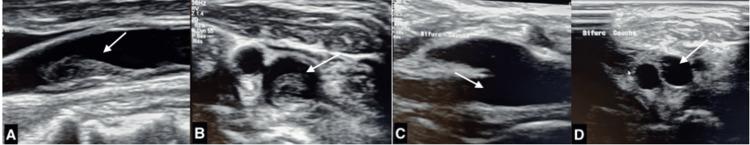

METHODS

A retrospective study was conducted over a 17-month period (2023-2024) at Ibn Rochd University Hospital, including patients with acute ischemic stroke and FFT diagnosed via computed tomography angiography (CTA) and/or duplex ultrasound (DUS). Collected data included age, NIHSS score at admission, etiological workup, and both clinical and imaging outcomes. Therapeutic management was guided by stroke severity, hemorrhagic risk, availability of treatment modalities, and the results of the etiological workup.

RESULTS

Among 940 ischemic stroke cases, FFT was identified in eight patients (0.8%), with a mean age of 50.6 years. Atherosclerosis was the predominant etiology. The thrombus was most frequently localized in the carotid arteries, but also involved the brachiocephalic and vertebral arteries. No patients received intravenous thrombolysis due to concerns regarding embolization risk. Medical management was applied in all cases, with six patients receiving anticoagulation therapy, and five of them receiving combined antiplatelet therapy and statins. One patient underwent delayed carotid endarterectomy following stroke recurrence. At three months, thrombus resolution was complete in four cases, while the remaining patients exhibited partial regression.